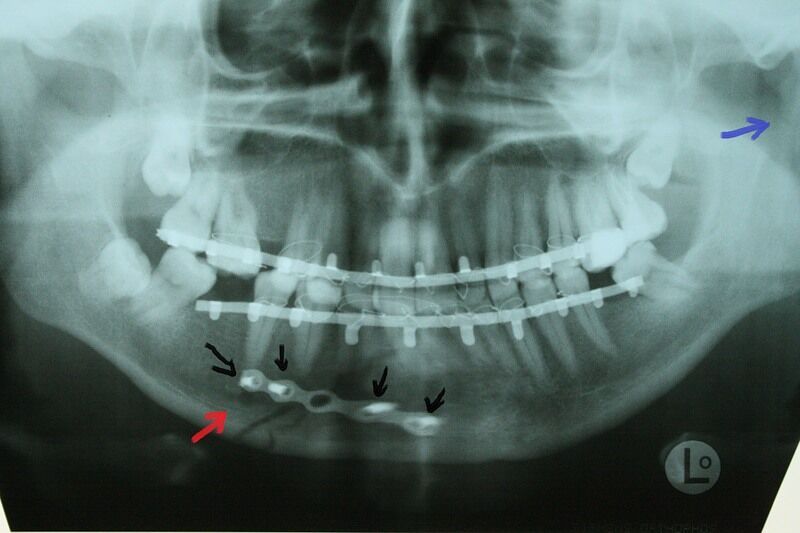

Не чувствую челюсти

Не чувствую челюсти 108 фотографий